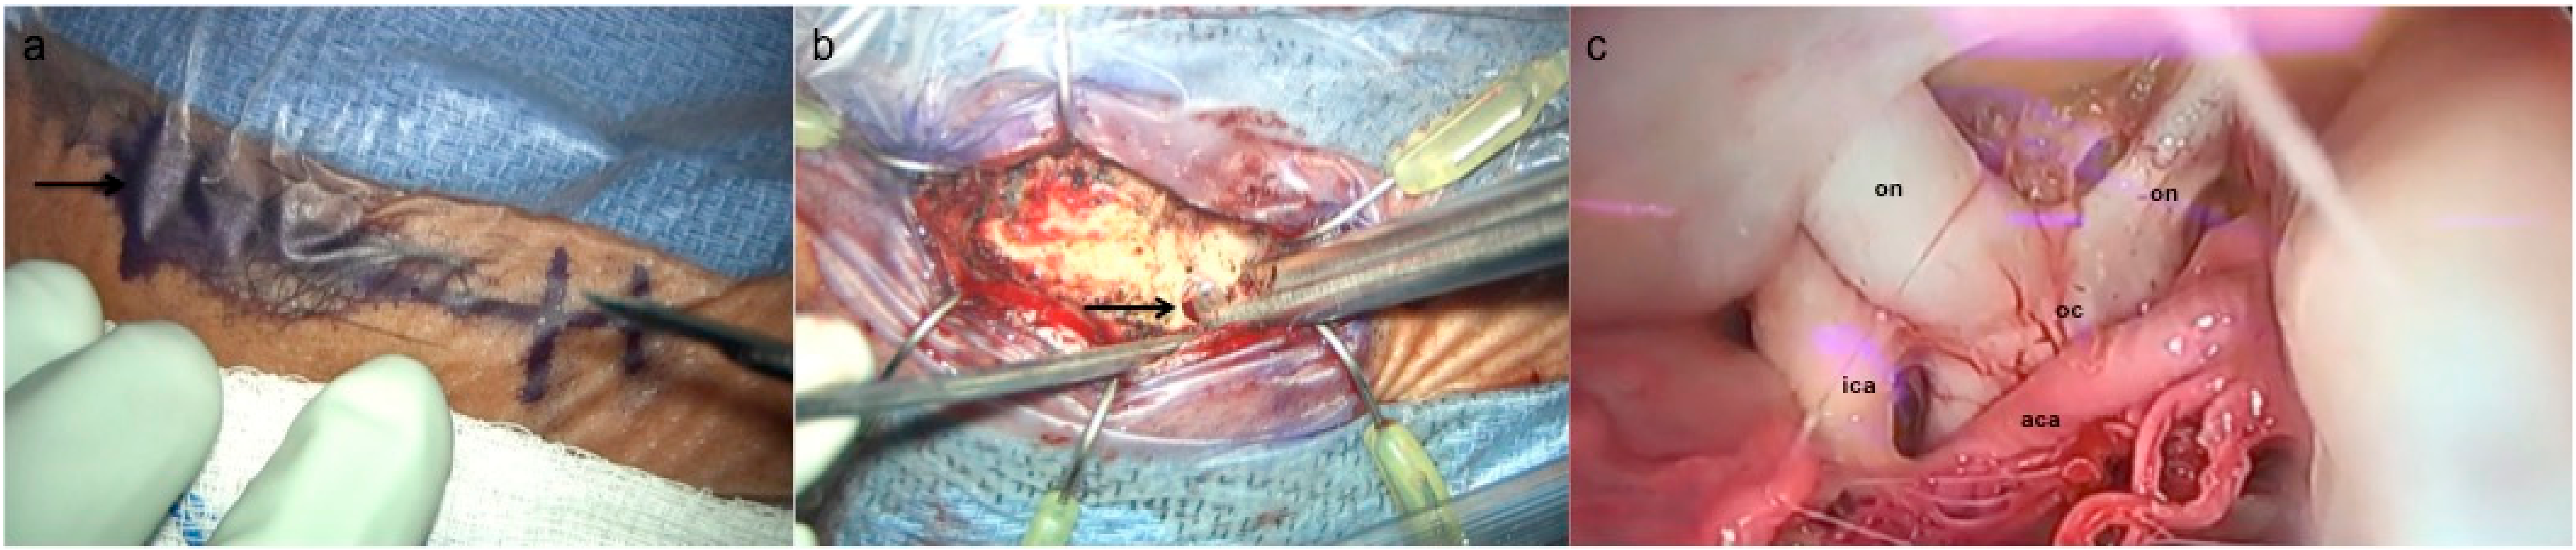

3.2. Supraorbital Craniotomy

4. Adjunctive Treatment Modalities